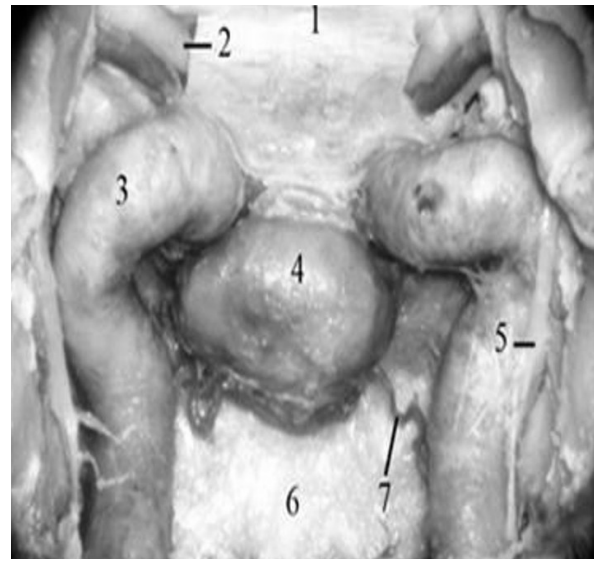

A dissecção expõe estruturas envolvidas nas abordagens transesfenoidais.

A estrutura 5 faz parte do sistema autonômico.

A abertura da região 1 resulta na exposição do espaço subaracnóideo da fossa anterior.

A estrutura 7 pode ter origem do tronco inferolateral.